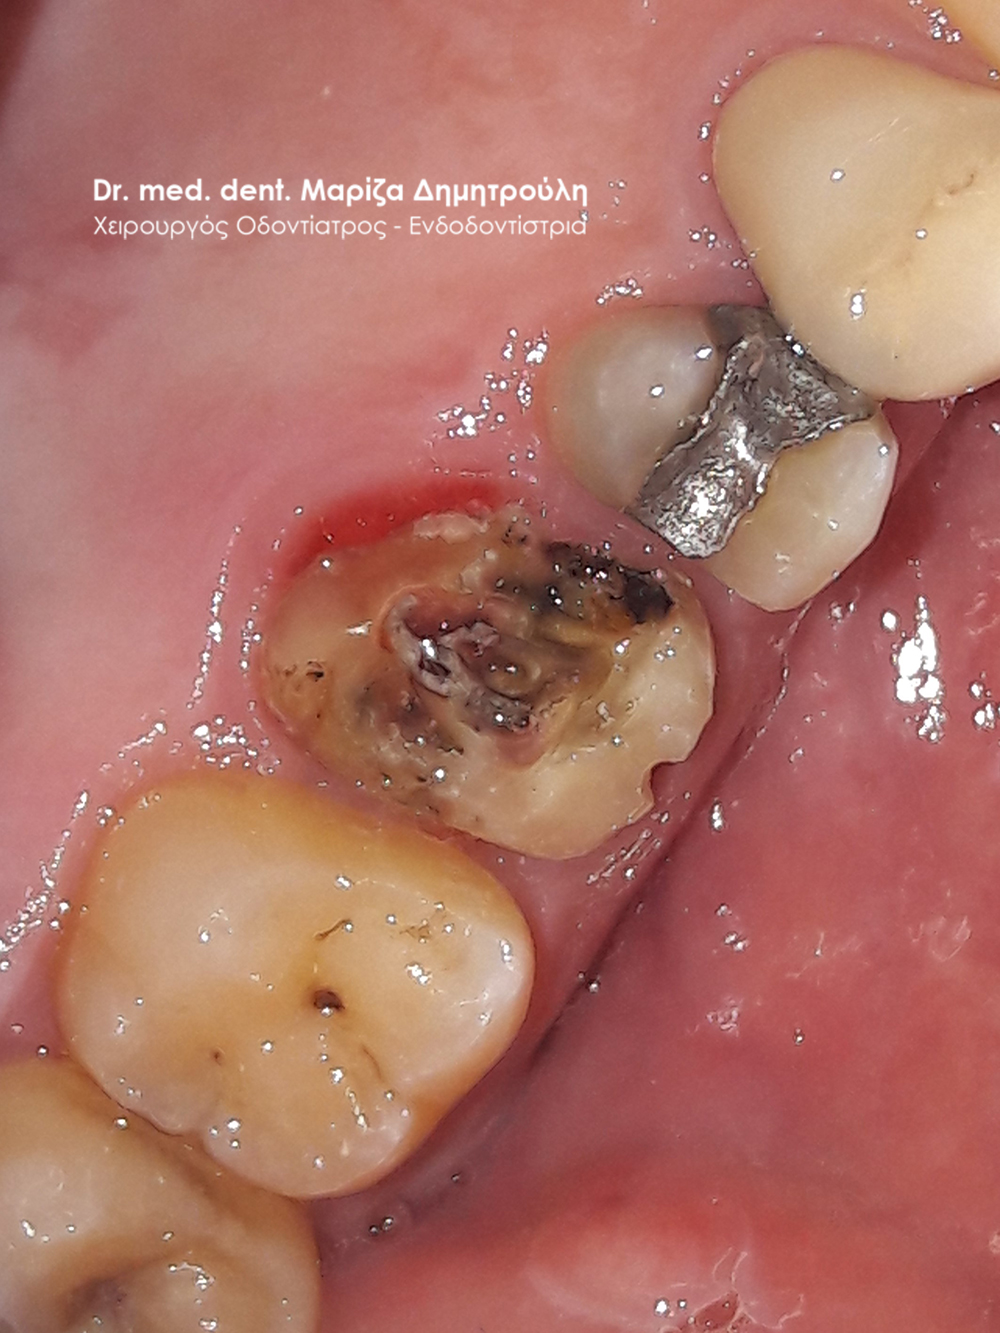

Μετά τη χορήγηση τοπικής αναισθησίας αφαιρέθηκε το παλιό σφράγισμα και εντοπίστηκαν οι ριζικοί σωλήνες του δοντιού (βλέπε φωτογραφία). Μετά την κατάλληλη επεξεργασία των ριζικών σωλήνων και εφόσον το δόντι ήταν ασυμπτωματικό η απονεύρωση ολοκληρώθηκε με την έμφραξη των ριζικών σωλήνων με ειδικό εμφρακτικό υλικό.

Εικόνα του δοντιού μετά τη διάνοιξή του και την επεξεργασία των ριζικών σωλήνων του δοντιού

Κλινική εικόνα του δοντιού με το υλικό έμφραξης στους ριζικούς σωλήνες του

Αποκατάσταση του δοντιού με λευκό σφράγισμα ρητίνης